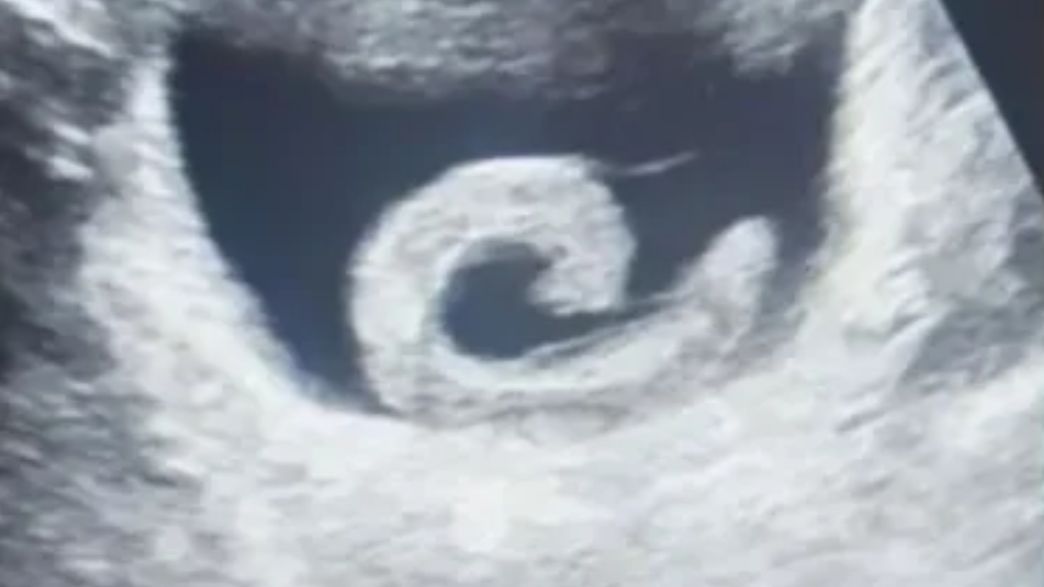

הכאב הפך לבלתי נסבל ולג'נג לא נותרה ברירה אלא לפנות לחדר המיון בבית חולים מקומי. הרופאים הופתעו לשמוע את דבריו, ערכו בדיקת אולטרסאונד ואישרו שאכן יש עלוקה בתוך שלפוחית השתן שלו. הצוות הרפואי נערך מיד לניתוח חירום.